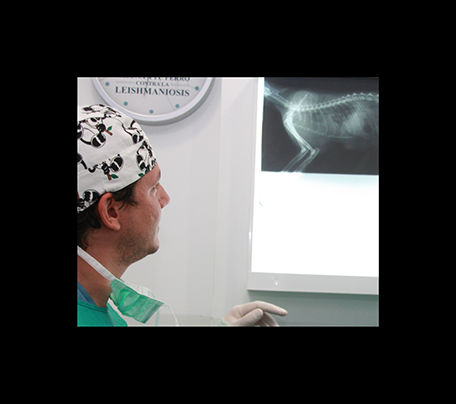

radiología

La radiologia es imprescindible en traumatologia y en algunos diagnosticos, ya sea mediante radiologia simple ó de contraste.

traumatología

En clinican podemos tratar las diversas afecciones que pudan afectar a huesos y articulaciones